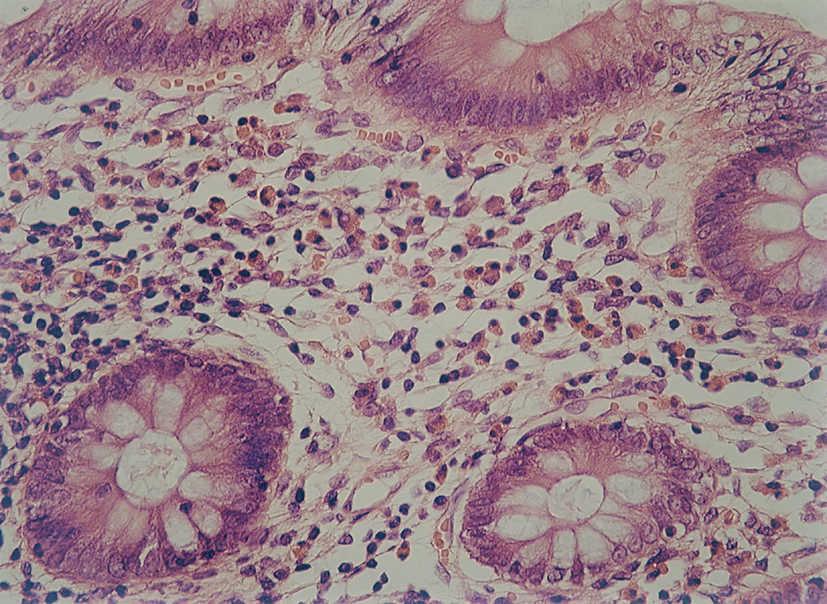

La anatomía patológica mostraba en todos los pacientes presencia de eosinófilos en mucosa esofágica en número superior a 20 por campo de gran aumento, de predominio peripapilar, así como hiperplasia epitelial (fig. 4). En 5 casos (45,45 %) se encontró un recuento aumentado de eosinófilos en antro gástrico y segunda porción de duodeno, por lo cual se realizó con posterioridad fibrocolonoscopia. En todos ellos se observaba una eosinofilia mucosa por encima de los valores normales en íleon terminal, colon y recto-sigma, que fue diagnosticada de gastroenteropatía eosinofílica con afectación generalizada (fig. 5).

Figura 5. Presencia de infiltrado eosinofílico en mucosa colónica de paciente afectado de esofagitis eosinofílica (gastroenteropatía eosinofílica). (Hematoxilina-eosina, x40.)